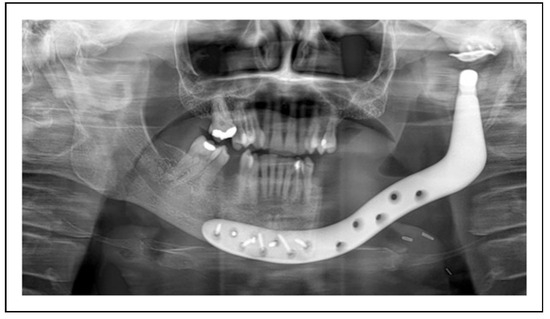

Two-Stage Regime, Patient 1